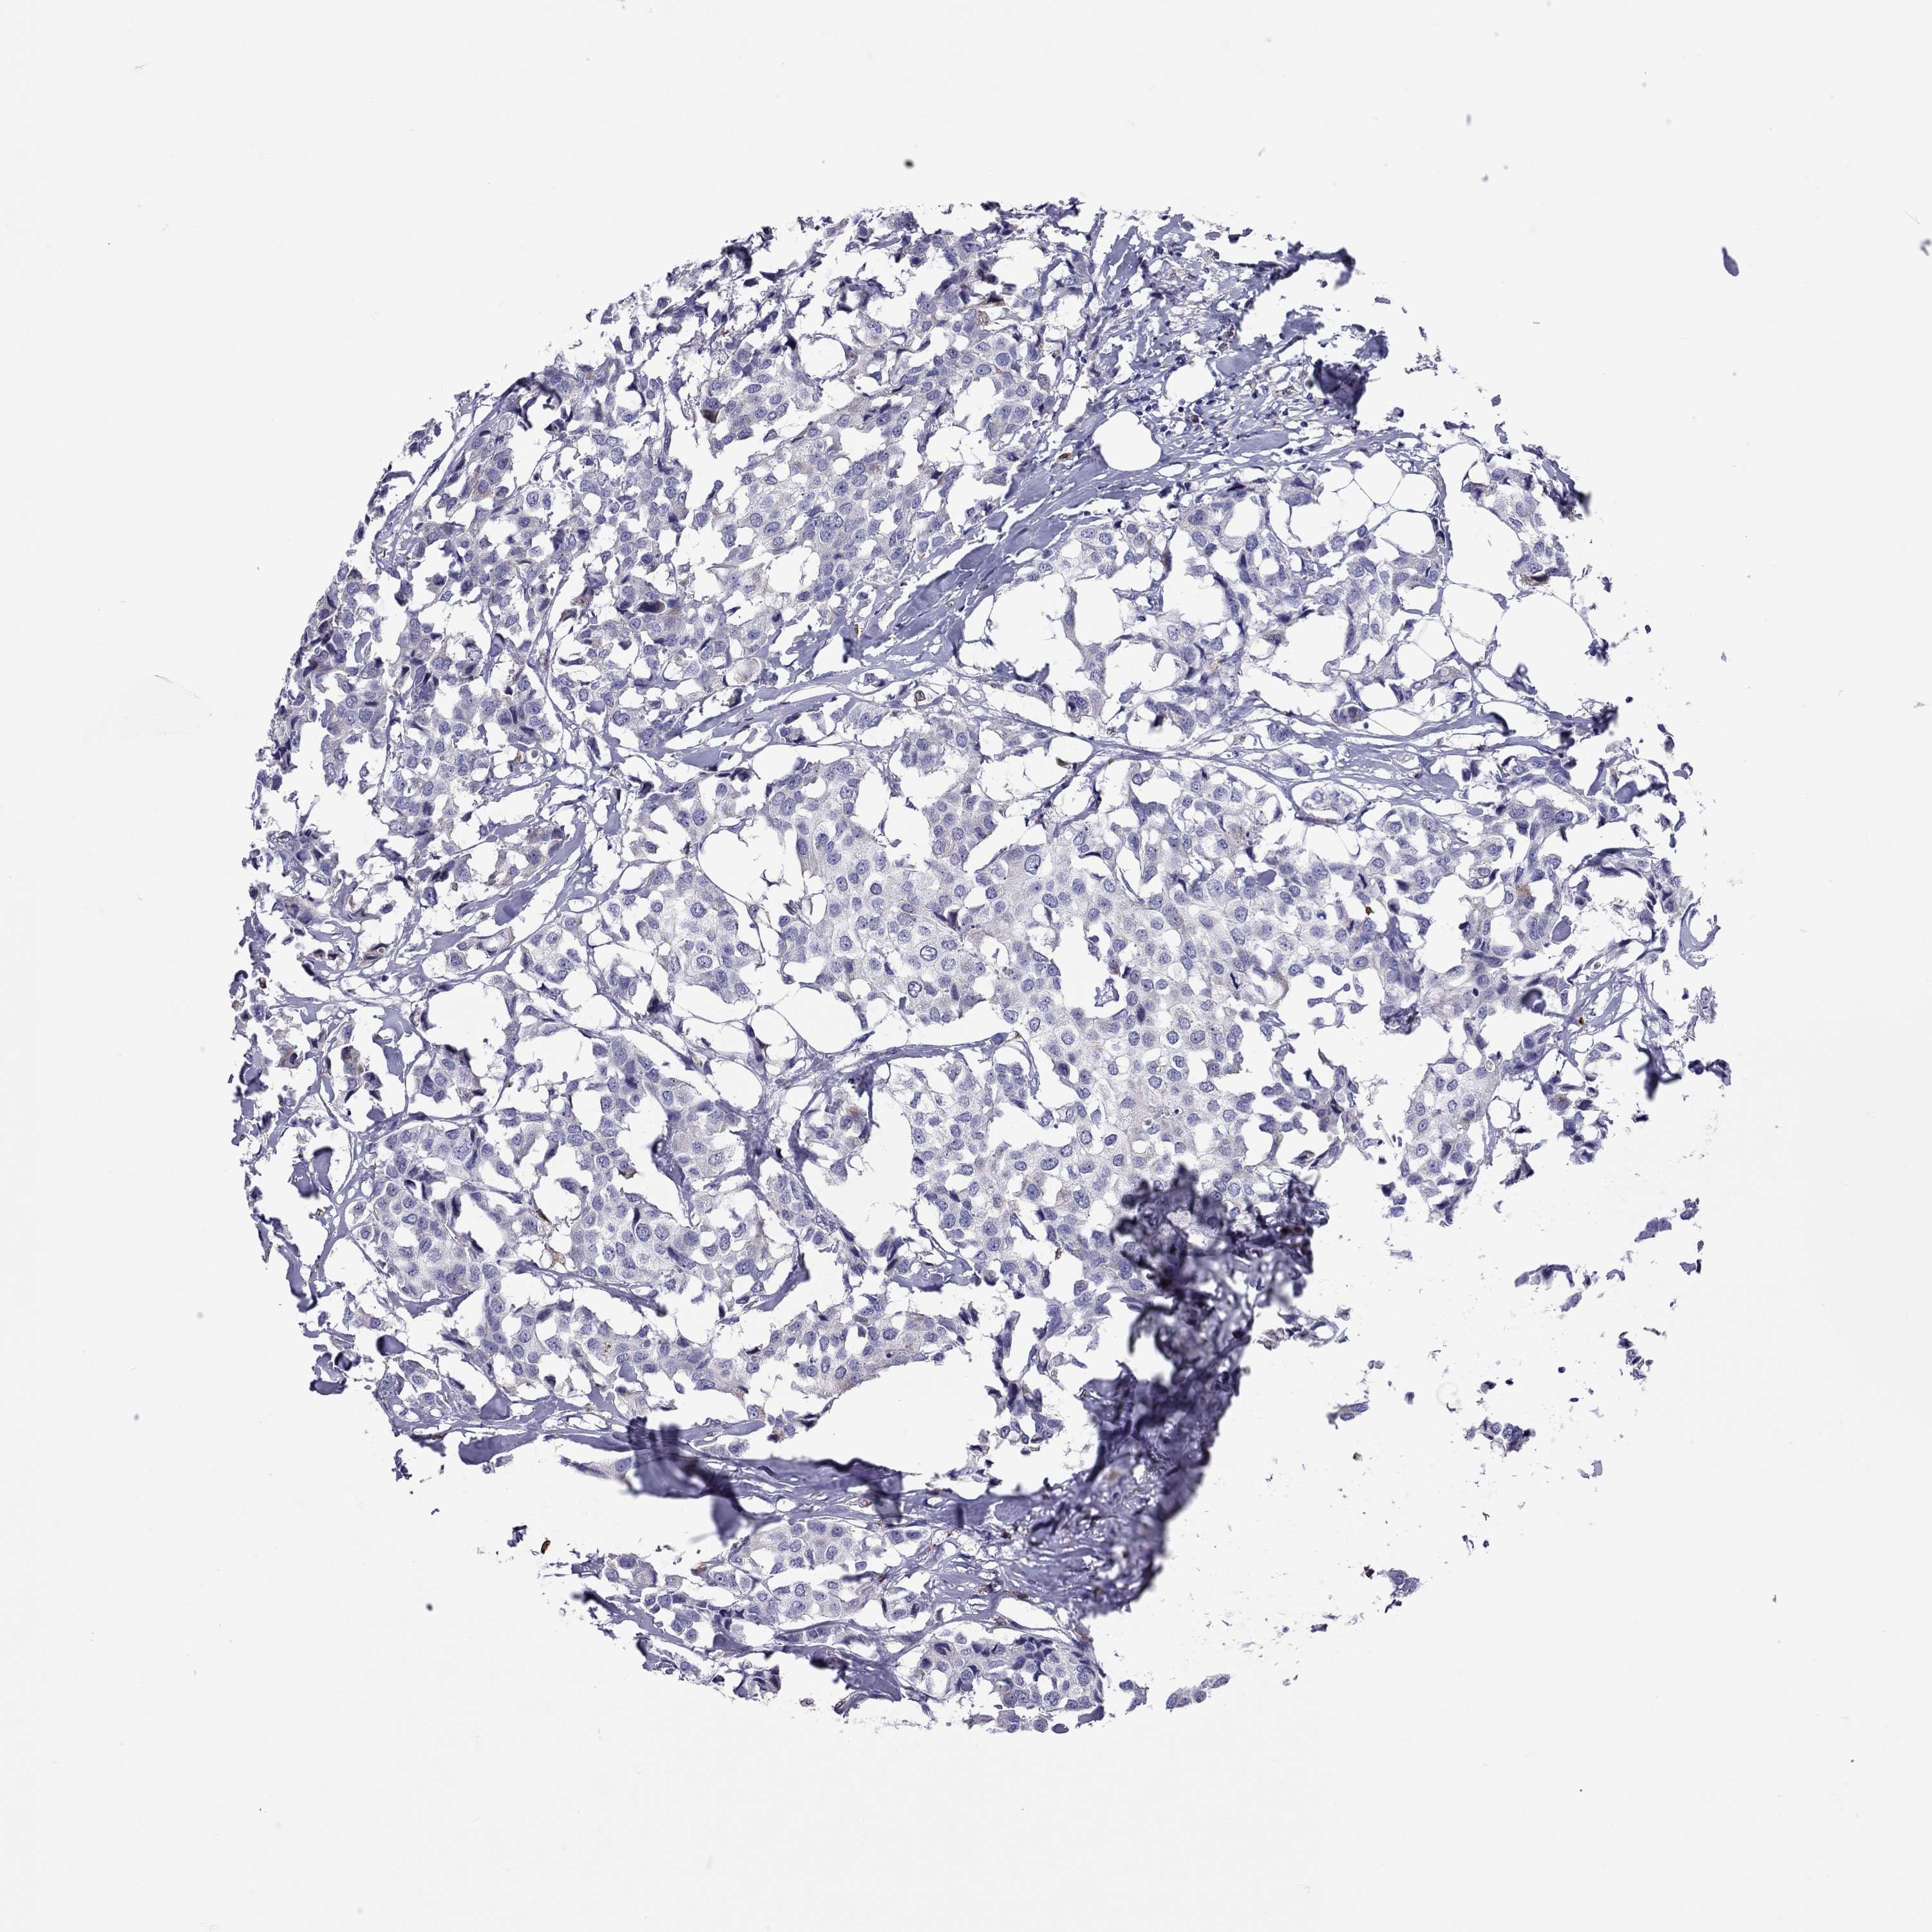

CANCER BREAST CANCER Show tissue menu

BRCA TCGA BRCA VALIDATION PROTEIN EXPRESSION